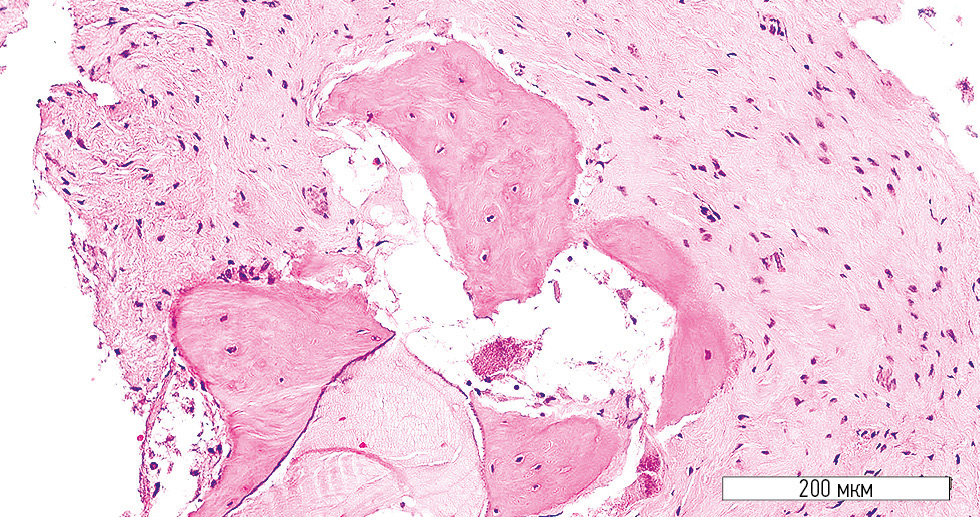

In the control group, numerous bone chip fragments were observed. Neither an obvious stromal component nor structured bone trabeculae were identified (Fig. 5). Isolated regions of active stromal component with pronounced vascularization were present. The bone trabeculae appeared immature, with osteoblasts and newly formed lacunae containing osteocytes (Fig. 6).

Fig. 5. Numerous bone fragments without stromal component or newly formed trabeculae (control group). Hematoxylin-eosin stain; original magnification ×200.

Fig. 6. Stromal component and newly formed immature bone trabecula (control group). Hematoxylin-eosin stain; original magnification ×400.